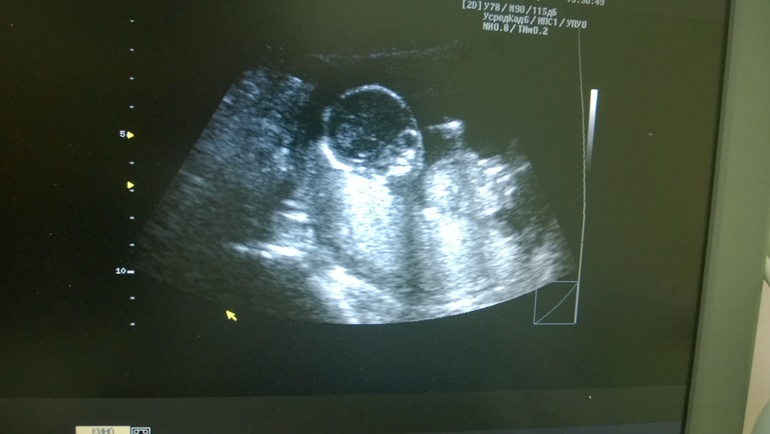

вчера были на узи, перед этим были беспокойные мыли( резко стала бодрой, пропала усталость и сонность. И вроде грудь с животом стали меньше).но узи показало что все у нас очень даже а еще, что мы ждем мальчика))

п.с.: На снимке ребеночек лежит на спинке и смотрит прямо на нас))